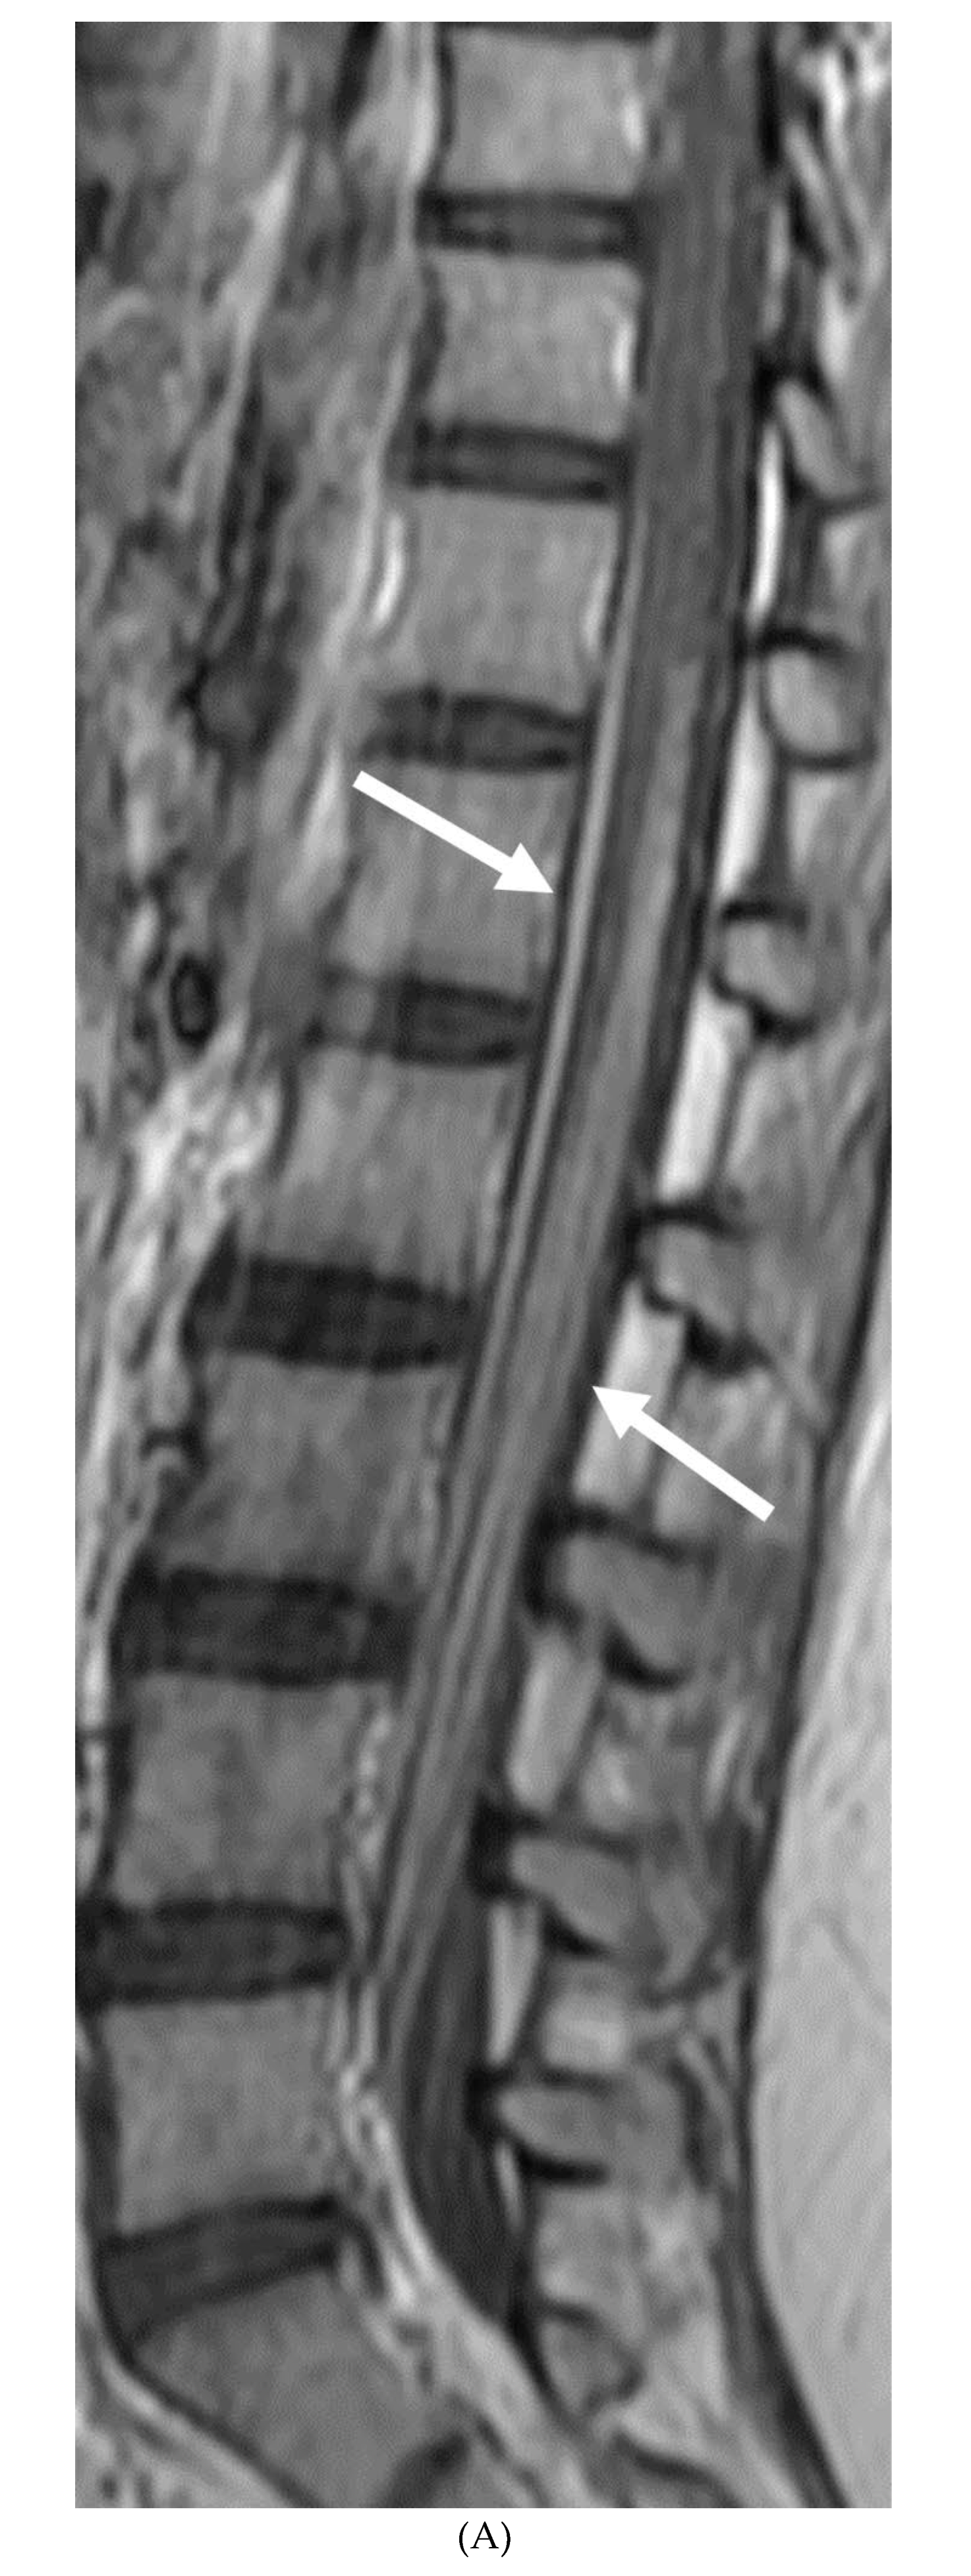

- Alkan O, Yildirim T, Tokmak N, Tan M. Spinal MRI findings of guillain-barré syndrome. J Radiol Case Rep. 2009;3(3):25-8. Epub 2009 Mar 1. PMID: 22470650; PMCID: PMC3303301. [CrossRef]

- Zuccoli G, Panigrahy A, Bailey A, Fitz C. Redefining the Guillain-Barré spectrum in children: neuroimaging findings of cranial nerve involvement. AJNR Am J Neuroradiol. 2011 Apr;32(4):639-42. Epub 2011 Feb 3. PMID: 21292802; PMCID: PMC7965877. [CrossRef]

- Fulbright RK, Erdum E, Sze G, Byrne T. Cranial nerve enhancement in the Guillain-Barré syndrome. AJNR Am J Neuroradiol. 1995 Apr;16(4 Suppl):923-5. PMID: 7611075; PMCID: PMC8332311.

- Yikilmaz A, Doganay S, Gumus H, Per H, Kumandas S, Coskun A. Magnetic resonance imaging of childhood Guillain-Barre syndrome. Childs Nerv Syst. 2010 Aug;26(8):1103-8. Epub 2010 Jun 17. PMID: 20556395. [CrossRef]

- Byun WM, Park WK, Park BH, Ahn SH, Hwang MS, Chang JC. Guillain-Barré syndrome: MR imaging findings of the spine in eight patients. Radiology. 1998 Jul;208(1):137-41. PMID: 9646804. [CrossRef]